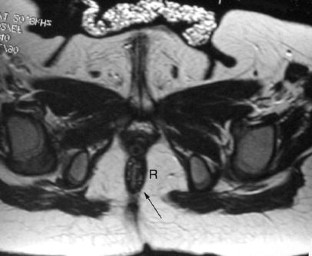

Fig. 1